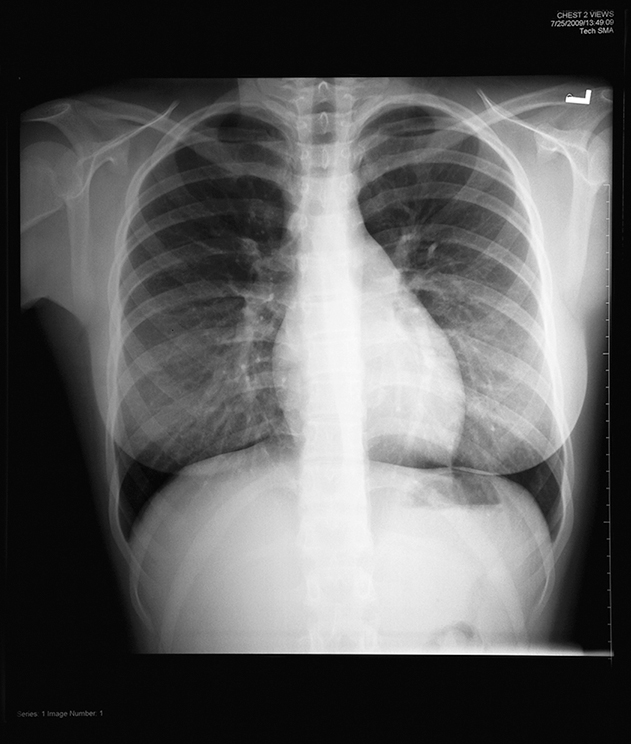

Radiography is the making of records, known as radiographs, of internal structures of the body by passage of x-rays or gamma rays through the body to act on, historically, specially sensitized film or, most commonly, on a digital imaging plate or detector. In the diagnostic radiography department, images are created using x-rays that pass through the body (Fig. 1.2). In addition, very-high-energy x-rays are used in the radiation therapy department for the treatment of many forms of cancer. In both of these departments, proper radiation protection is essential.

An R.T. specializing in the use of x-rays to create images of the body is known as a radiographer (Fig. 1.5). Radiographers perform a wide variety of diagnostic x-ray procedures, including examinations of the skeletal system, the chest, and the abdomen. They administer contrast media to permit visualization of the gastrointestinal (GI) tract and the genitourinary system. They also assist the radiologist during more specialized contrast media procedures, such as those used to visualize the spinal cord (myelography) and the joint spaces (arthrography).